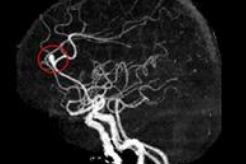

뇌동맥류를 정확히 진단하기 위해서는 정밀한 뇌 영상 검사가 필수적입니다. 대표적인 검사 방법으로는 전산화단층촬영(CT), CT 혈관조영술(CTA), 자기 공명영상(MRI), 자기 공명혈관조영술(MRA) 등이 있습니다. 특히, 뇌혈관조영술은 가장 정확한 진단 방법으로 치료 계획 수립에 중요한 정보를 제공합니다.